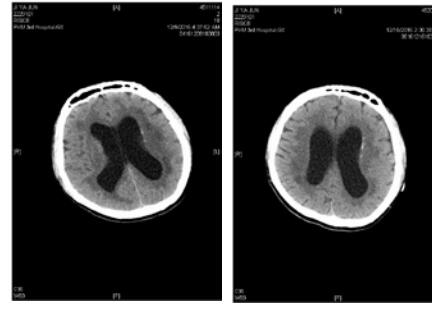

患者,男,31岁,既往体健。因“间断发热、咳嗽10 d,昏迷16 h”于2016年12月9日入院。患者2016-11-30无诱因出现咳嗽、发热,抗感染治疗3 d后,症状好转。2016-12-6患者再次出现上述症状,最高体温38℃,伴头痛。2016-12-8 19:31于本院就诊期间出现意识模糊,瞻妄,次日02:15患者深昏迷,呼之不应。查体:体温38.5℃,脉搏131次/min,呼吸29次/min,血压126/56 mmHg(1 mmHg=0.133 kPa), 心、肺、腹未见异常。专科情况:深昏迷,双侧瞳孔不等大,左侧d=5.5 mm, 右侧d=6.0 mm, 双侧对光反射消失,疼痛刺激无反应,角膜反射未引出,脑神经查体不合作,四肢肌力查体不合作,双上肢肌张力高,双下肢肌张力正常,双侧膝、跟腱反射亢进,踝阵挛,颈强直,克氏征阳性、布氏征阳性。颅脑CT示双侧侧脑室低密度影,颅内感染?双侧侧脑室扩张。血常规:白细胞15.43×109/L,中性粒细胞百分比4.62%;降钙素原3.74 ng/mL, 12月9日行腰椎穿刺抽出淡黄色微混脑脊液,压力>300 cmH2O(1cmHg=0.098kPa), 脑脊液常规:细胞总数864 ×106/L,白细胞818×106/L,多核细胞80%,单核细胞20%,生化:氯113.3 mmol/L,葡萄糖1.00 mmol/L,总蛋白258.0 g/L,革兰染色、墨汁染色、抗酸染色阴性,脑脊液培养结果阴性。血培养结果示:肺炎链球菌。诊断为化脓性脑膜炎,病原菌为肺炎链球菌。给予降颅压,抗感染治疗后,症状好转,2016-12-12患者疼痛刺激有反应。2016-12-20神志转清,可按指令发出动作,但遗留有双侧动眼神经损伤,表现为双侧瞳孔散大,双侧对光反射消失,双侧眼睑下垂,左侧明显,双侧瞳孔各方位(除外展位外)运动不良;此外,合并双侧视神经、左侧面神经损伤,表现为无光感,左侧额纹消失,左侧鼻唇沟略浅。2016-12-26患者恢复部分光感,但视野缺损,无法分辨颜色。双侧动眼神经损伤及左侧面神经损伤未见明显改善,查体脑膜刺激征仍阳性。2016-12-15复查颅脑CT较前无明显变化。2016-12-27颅脑磁共振示脑积水,颅底感染,考虑患者动眼神经及其余脑神经损伤与高颅压压迫脑神经及颅底感染侵及脑神经有关,建议患者外院行脑室穿刺引流术进一步治疗。

| 图 1 左侧为2016年12月8日我院颅脑CT,右侧为2016年12月15日我院复查颅脑CT,两次颅脑CT均提示双侧侧脑室扩张,无明显变化 |